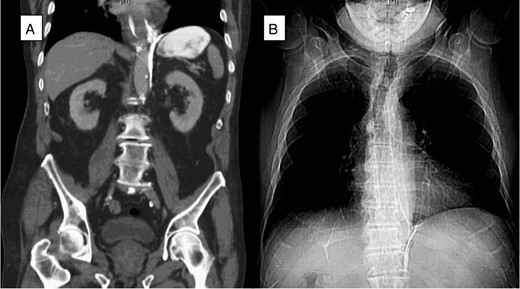

An 81-year-old male presented to the emergency department with hematemesis and epigastric pain. On the evening of presentation, the patient reported difficulty in swallowing a piece of meat during dinner, which led to several episodes of retching followed by bloody emesis. His medical history was significant for extensive cardiovascular diseases including hypertension, stroke and pulmonary embolism for which an inferior vena cava filter had been in place. He had also undergone a carotid endarterectomy and taking daily aspirin. On initial presentation, the patient was afebrile, in sinus rhythm and normotensive. He had several episodes of hematemesis in the emergency department, and a nasogastric tube was placed with 500 ml of sanguineous output. Chest examination did not reveal any subcutaneous air, and lungs were clear bilaterally. On abdominal exam, however, the patient had tenderness to deep palpation of the epigastrium without any signs of peritonitis. Laboratories were significant for leukocytosis to 16.5 × 109/l and hemoglobin of 11.6 × 109/l. A computed tomography (CT) scan of the abdomen and pelvis with oral contrast was performed, which showed extraluminal contrast extending around the esophagus and around the left crus of the diaphragm that was compatible with esophageal perforation (Fig. 1A). The patient was resuscitated with fluids, started on broad spectrum antibiotics and after reviewing the CT scan was taken to the operating room for endoscopy, which revealed a 7-cm long esophageal perforation, starting at 29 cm and covered with blood clot. The gastroesophageal junction was identified at 42 cm from the incisors. About 1 l of blood was suctioned from the stomach and the GE junction was again visualized in retrograde view for possible involvement. There was no evidence of a tear in the gastric wall and no active bleeding was visualized. A partially covered self-expanding metal WallFlex stent (Boston Scientific) was introduced over a wire into the esophagus and deployed, covering the entire length of the perforation (Fig. 1B). The stent was bridled in place with an umbilical tape and we proceeded with an exploratory laparoscopy, which did not reveal any evidence of purulence near the area of the hiatus. A laparoscopic feeding jejunostomy tube was also placed at the time. Postoperative course was uneventful. The patient was kept nil per os for the next month, on tube feeds and antibiotics. His leukocytosis resolved over the ensuing days and his hemoglobin remained stable. A month later he presented to the hospital for esophageal stent removal. After endoscopically removing the stent, small healing ulcerations were identified in the area of previous perforation (Fig. 2A and B). An esophagram was performed using water soluble Omnipaque contrast to evaluate for a possible leak at the ulceration sites; however, no frank leak was found (Fig. 2C). The patient was then started on a clear liquid diet and discharged home. He was slowly advanced to a regular diet over the next several weeks which he tolerated well without any further complications.

(A) A CT scan of the abdomen (coronal plane) demonstrated extraluminal contrast extending around the esophagus and around the left crus of the diaphragm. (B) Chest X-ray after esophagogastroduodenoscopy (EGD) and esophageal stent placement with stent in good position.